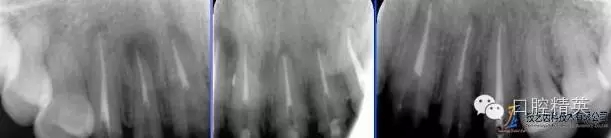

術(shù)后根尖片

PD纖維樁樹脂修復(fù)